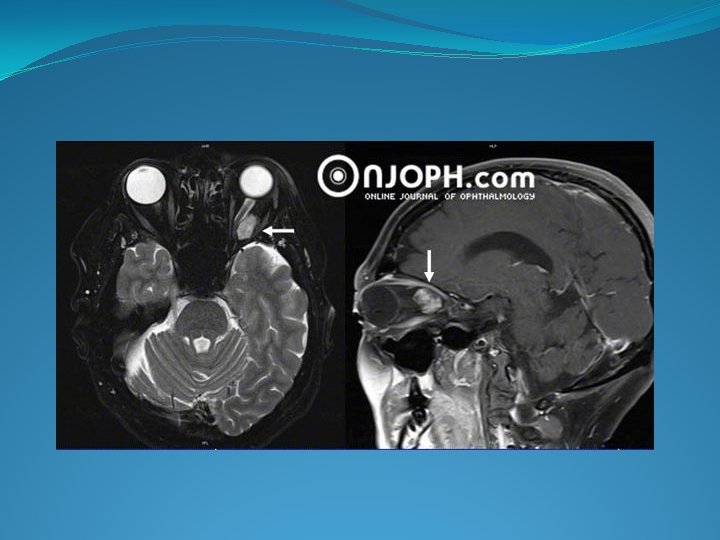

� Clinique: Signes d’appel ++ : Exophtalmie axile, modérée (Svt), non pulsatile, indolore et irréductible. Baisse de l’acuité visuelle Strabisme F. O : Œdème papillaire ou atrophie optique. � Imagerie: TDM crânienne : exophtalmie N. O augmenté de volume éventuelle extension au chiasma et retentissement sur le système ventriculaire. IRM : dans les gliomes de la portion intracanalaire du nerf optique

�Evolution: -lente. -pronostic peut être péjoratif et dépend de deux facteurs : Association à la maladie de Von Recklinghausen extension au chiasma /a l autre nerf optique / 3 eme Ventricule /hypothalamus.

�Imagerie : Radio standard: >Souvent normale. >Elargissement ou rétrécissement ; Ostéocondensation du canal optique. � Echo orbitaire: Tm intra conique. � TDM: >Epaississement fusiforme, irrégulier+/– centré /NO. >Hyperdense spontanée. forte rehaussement après injection > En coupe axiale transverse : image typique « rail de tramway � IRM +++++ -Exploration parfaite de la potion intracanalaire+++. -Précise l’extension post e la Tm. >Tm prenant fortement le contracte au Gadolinium. >Nerf optique normal, bien visible dans la Tm qui est souvent excentrée par rapport à lui.